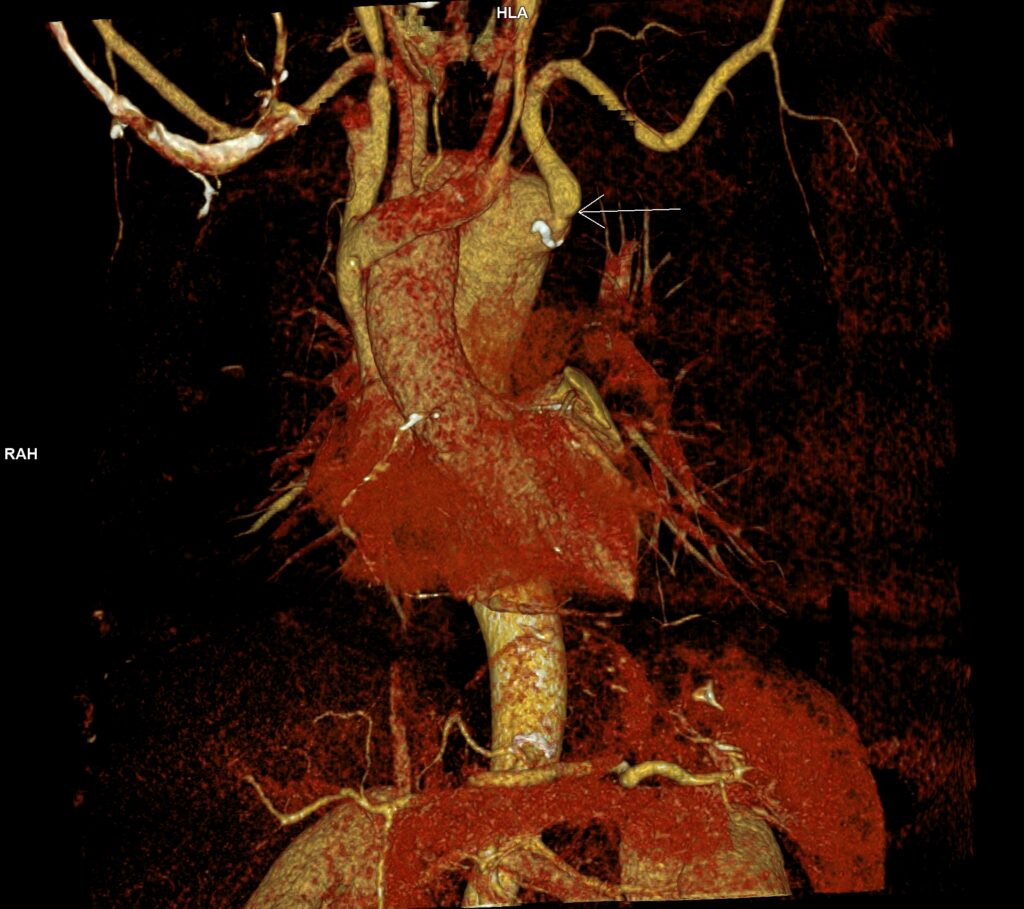

Figura 2: reconstrucție dinspre anterior de tip VRT crosa aortică la dreapta și diverticulul de origine a arterei subclavii stângi

Figura 3: reconstrucție dinspre posterior de tip VRT crosa aortică la dreapta și diverticulul de origine a arterei subclavii stângi

Discuţie caz nr 130: examinare efectuată pentru suspiciune de dilatație anevrismală a aortei ascendente; achiziția a fost realizată cu sincronizare ECG pentru vizualizare optimă a valvei aortice și a peretelui aortic și surpriza a fost un arc aortic la dreapta cu aortă descendentă toracică la dreapta și o dilatație anevrismală / diverticul posterior de trahee și esofag și anterior de coloana vertebrală din care are origine arteră subclavie stânga (Diverticulul Kommerell).

DE LUAT ACASĂ!!! Achiziția cu sincronizare ECG la examinarea AngioCT aortă toracică este indicat / obligatoriu sa fie utilizată la pacienții care sunt trimiși la examinare CT pentru evaluarea aortei toracice. Diverticulul Kommerell se referă de obicei la configurația bulboasă a originii unei artere subclaviculare stângi aberante în contextul unui arc aortic drept. Cu toate acestea, a fost descrisă inițial ca o protuberanță diverticulară la originea unei artere subclaviculare drepte aberante cu un arc aortic stâng și se observă și în arterele vertebrale drepte aberante (arteria lusoria vertebrală).